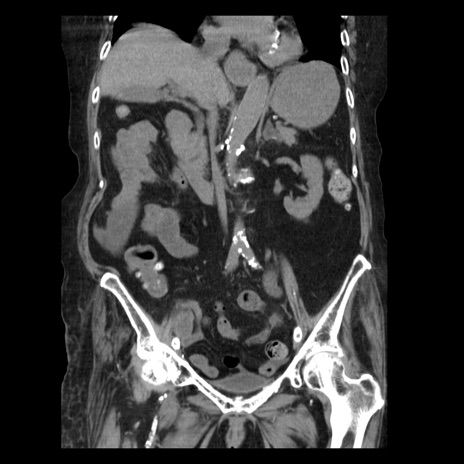

症例14(冠状断像)

【症例】 90歳代女性

【主訴】 腹痛・嘔吐

【現病歴】今朝から左側腹部痛を認めた。 経過観察していたが、嘔吐を認めたため来院。

【既往歴】 子宮癌術後

【身体所見】 意識清明、BP 127/54mmHg、P 98bpm Sp02 95%(RA)、BT 35.8°C、腹部平坦・軟腸ぜん動音聴取良好、右下腹部圧痛(+) 反跳痛なし

【データ】WBC 9800、CRP 0.46